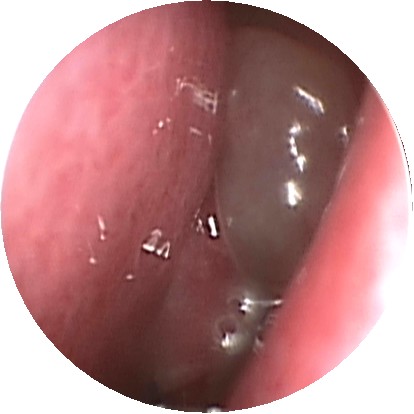

在治疗前做检查,有助于医生比较好的把握患者的病情,制定出比较符合患者病情的治疗方案。比如鼻息肉,一般会进行鼻内镜检查加ct检查,用来明确患者鼻息肉的位置、大小以及是单发还是多发等信息,防止出现漏诊,保证治疗的效果。

鼻内窥镜检查下的鼻息肉